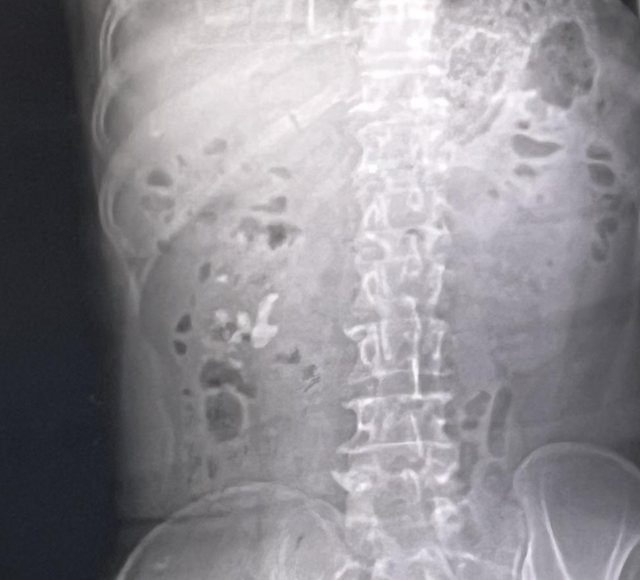

駐馬店市中心醫院近期收治一名因長期飲水不足、飲食失衡導致腎結石的12歲患者,刷新了公眾對結石疾病低齡化趨勢的認知。該院婦女兒童醫院成人、小兒泌尿外科主任徐海亮指出,腎結石的形成與日常飲食習慣密切相關,平時要注意飲水量控制、膳食結構調整、礦物質攝入,建立"吃出來的健康防線"。

徐海亮說,腎結石的形成與多種因素有關,包括尿液中礦物質的濃度過高、尿液酸堿度失衡等。當尿液中的某些成分,如鈣、草酸、尿酸等濃度過高時,它們可能會結晶并聚集成團,最終形成結石。腎結石的癥狀多種多樣,可能包括腰痛、血尿、尿頻、尿急、尿痛等。若結石較大或卡在尿路中,還可能引發腎積水、腎功能受損等嚴重后果。所以預防腎結石需要對日常飲食和生活方式進行干預。

徐海亮提醒:“得了腎結石之后,一定要注意改變平常的飲食習慣和飲水習慣,注意增多和減少這四個字,首先要增多平常的飲水量,直至使尿液顏色變清亮,這是初步評判多飲水的一個標準。同時要減少含鈣食物的攝入和高草酸食物的攝入,減少動物內臟、啤酒等高嘌呤食物攝入,平常要注意低鹽飲食,減少高熱量飲料攝入。如果結石直徑小于六毫米,可以通過運動、跑跳、喝水,配合藥物治療,促進結石的自然排出。如果結石直徑大于六毫米,建議體外碎石或者進行手術治療。”